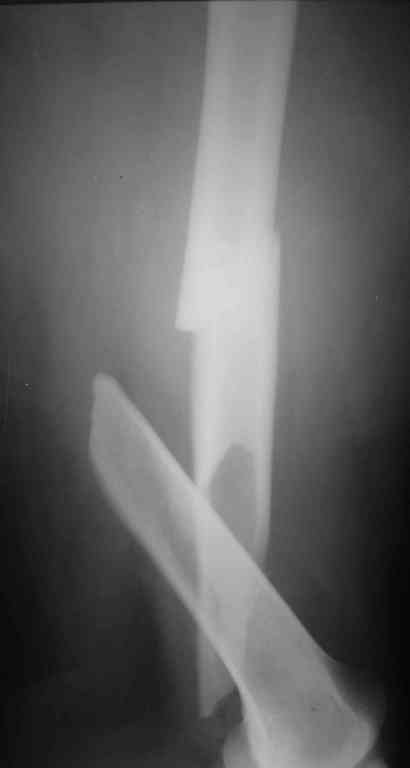

Re: переломы обоих бедер

По представленному снимку выполнял бы антеградное введение стержня, длинна дистального отломка позволяет. Только блокирование более чем в одной плоскости.